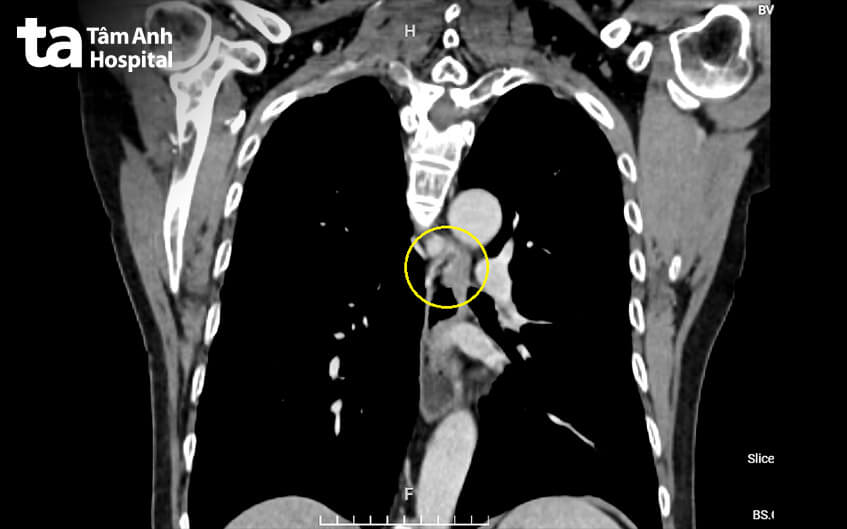

Ông Nguyễn Thái đến Bệnh viện Đa khoa Tâm Anh TP HCM khám do nuốt nghẹn, nấc cụt hơn ba tháng không rõ nguyên nhân. Kết quả chụp cắt lớp vi tính (CT) vùng bụng và ngực của ông cho thấy thành thực quản dày bất thường đoạn 1/3 giữa (ngang mức đốt sống ngực T6-7), chưa thấy xâm lấn động mạch chủ, khí quản và cơ quan lân cận.

Ngày 26/4, tiến sĩ, bác sĩ Đỗ Minh Hùng, Giám đốc Trung tâm Nội soi và Phẫu thuật Nội soi Tiêu hóa, cho biết ông Thái bị ung thư thực quản giai đoạn ba. Tổn thương thành thực quản của ông có kích thước 4 cm, đã ăn vào lớp cơ.